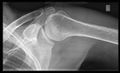

تصوير الكتف

أشعة إكس